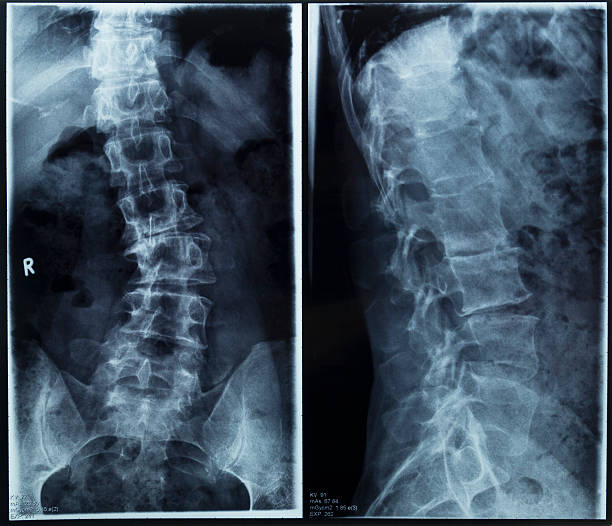

척추측만증은 척추의 공간 침범으로 인해 발생하는 질병으로, 이로 인해 척추의 굽힘이나 비틀림이 발생할 수 있습니다.